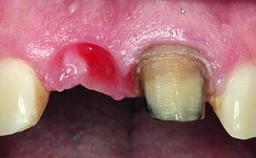

Replacement of a Failing Upper Left Central Incisor: Immediate Placement of an RC Bone Level Implant and Provisionalization

A healthy 23-year-old female patient was referred for a consultation on replacing tooth 21 with an implant-supported restoration. The patient had recently moved to the area and reported a history of endodontic and periodontal treatment for tooth 21. The tooth had been deemed non-restorable by her previous periodontist but since she was going to be moving, he recommended consulting to a dentist in her new city to continue her treatment. A review of her medical history yielded no significant findings and no known drug allergies. The analysis of her smile revealed a medium to high symmetrical smile line and a slightly discolored tooth 21.

Placement Protocol Immediate implant placement

Socket Integrity Damage to one or more bone walls

Bone Volume Damage to one or more socket walls